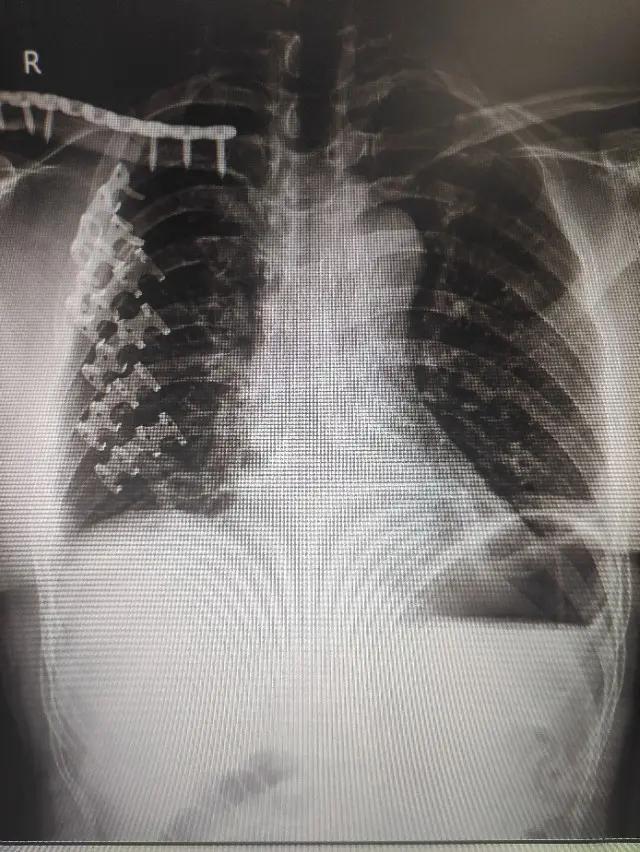

肋骨骨折是最常见的胸部外伤,肋骨骨折在全身的所有骨折中约占10-20%。

1、 骨折错位程度。如果骨折明显错位,可行手术治疗。

2、 骨折断裂根数。如果为单根肋骨骨折,可以选择保守治疗。若骨折根数较多,胸廓容易不稳定,需要手术治疗。